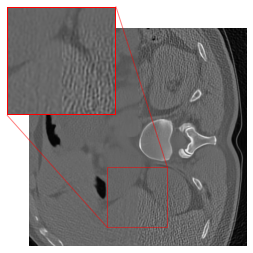

Figure 3 shows reconstruction results from the three networks for a test sample from the LoDoPaB-CT test dataset and one from the 2016LDCTGC dataset. All trained networks successfully improve the FBP reconstructions, as shown by the improved image quality and finer structural details.

Figure 3: Reconstruction results for two test samples from the LoDoPaB-CT test dataset (top row) and the 2016LDCTGC dataset (bottom row). The first column displays the ground truth, followed by the FBP in the second column. The next three columns present reconstructions by the Gaussian denoisers DRUNet, KBNet, and Restormer. Each pretrained denoiser model was trained for 96 epochs on 1791 image pairs from either the LoDoPaB-CT training dataset or the 2016LDCTGC dataset. The proposed two-stage method effectively enhances the FBP reconstructions in each case, as demonstrated by the PSNR and SSIM metrics provided below each subimage.